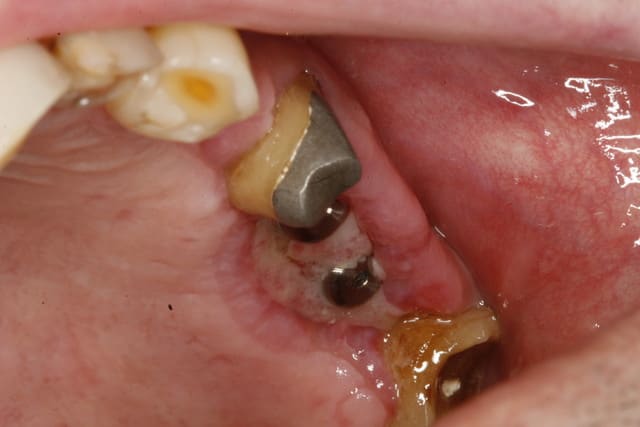

choses promises choses dues voici les photos du cas à J PLUS 18

mg 1015 ynvxwx - Eugenol